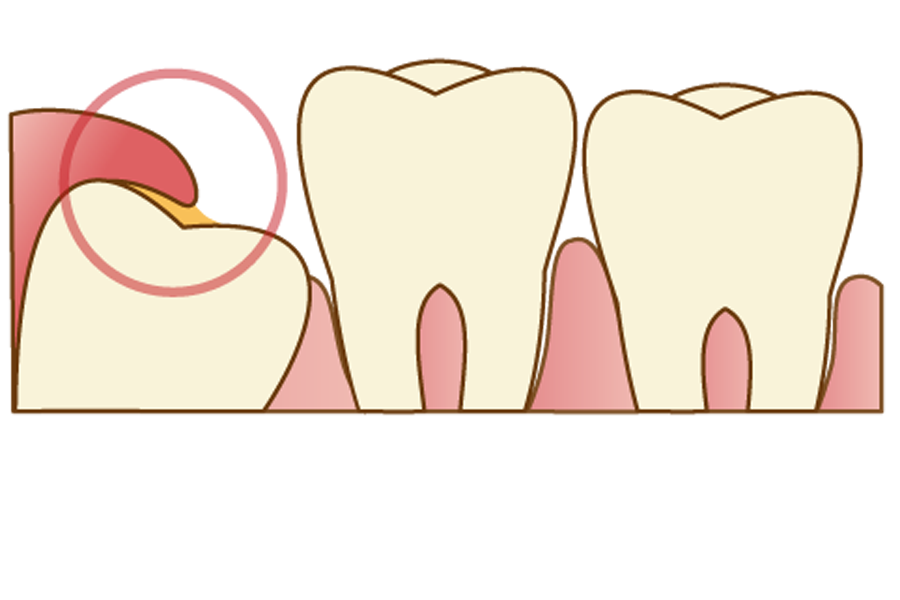

歯茎が上に覆いかぶさっている場合

歯茎が覆いかぶさっている親知らずの場合、歯茎と親知らずの間に汚れがたまりやすく、「智歯周囲炎」を起こしてしまうリスクが高いです。

智歯周囲炎とは、親知らずの周囲に起こる炎症のことで、重症化すると他の人が見てわかるくらいに顔が腫れたり、発熱・倦怠感といった全身症状が起こる場合もあります。

軽度の症状であれば、患部を清潔に保つことで解消されることがほとんどですが、何度も炎症や痛みを繰り返す場合は将来的なリスクを考慮して、早めの抜歯をおススメします。